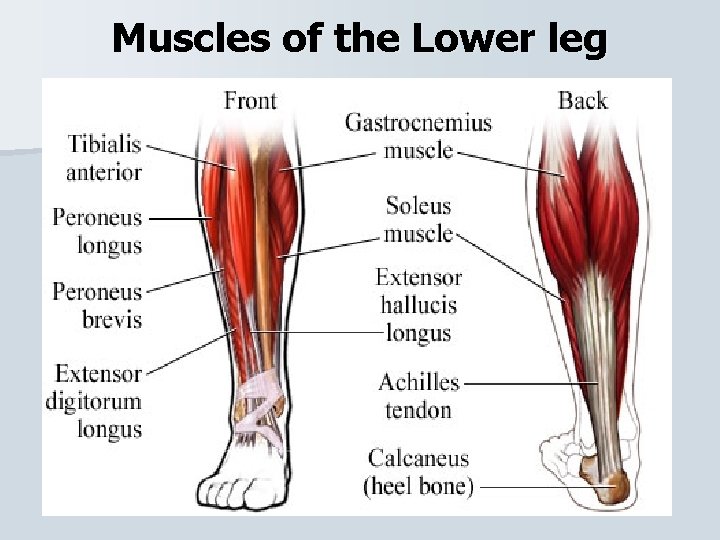

Muscles of the Lower leg

Muscles of the Lower Leg